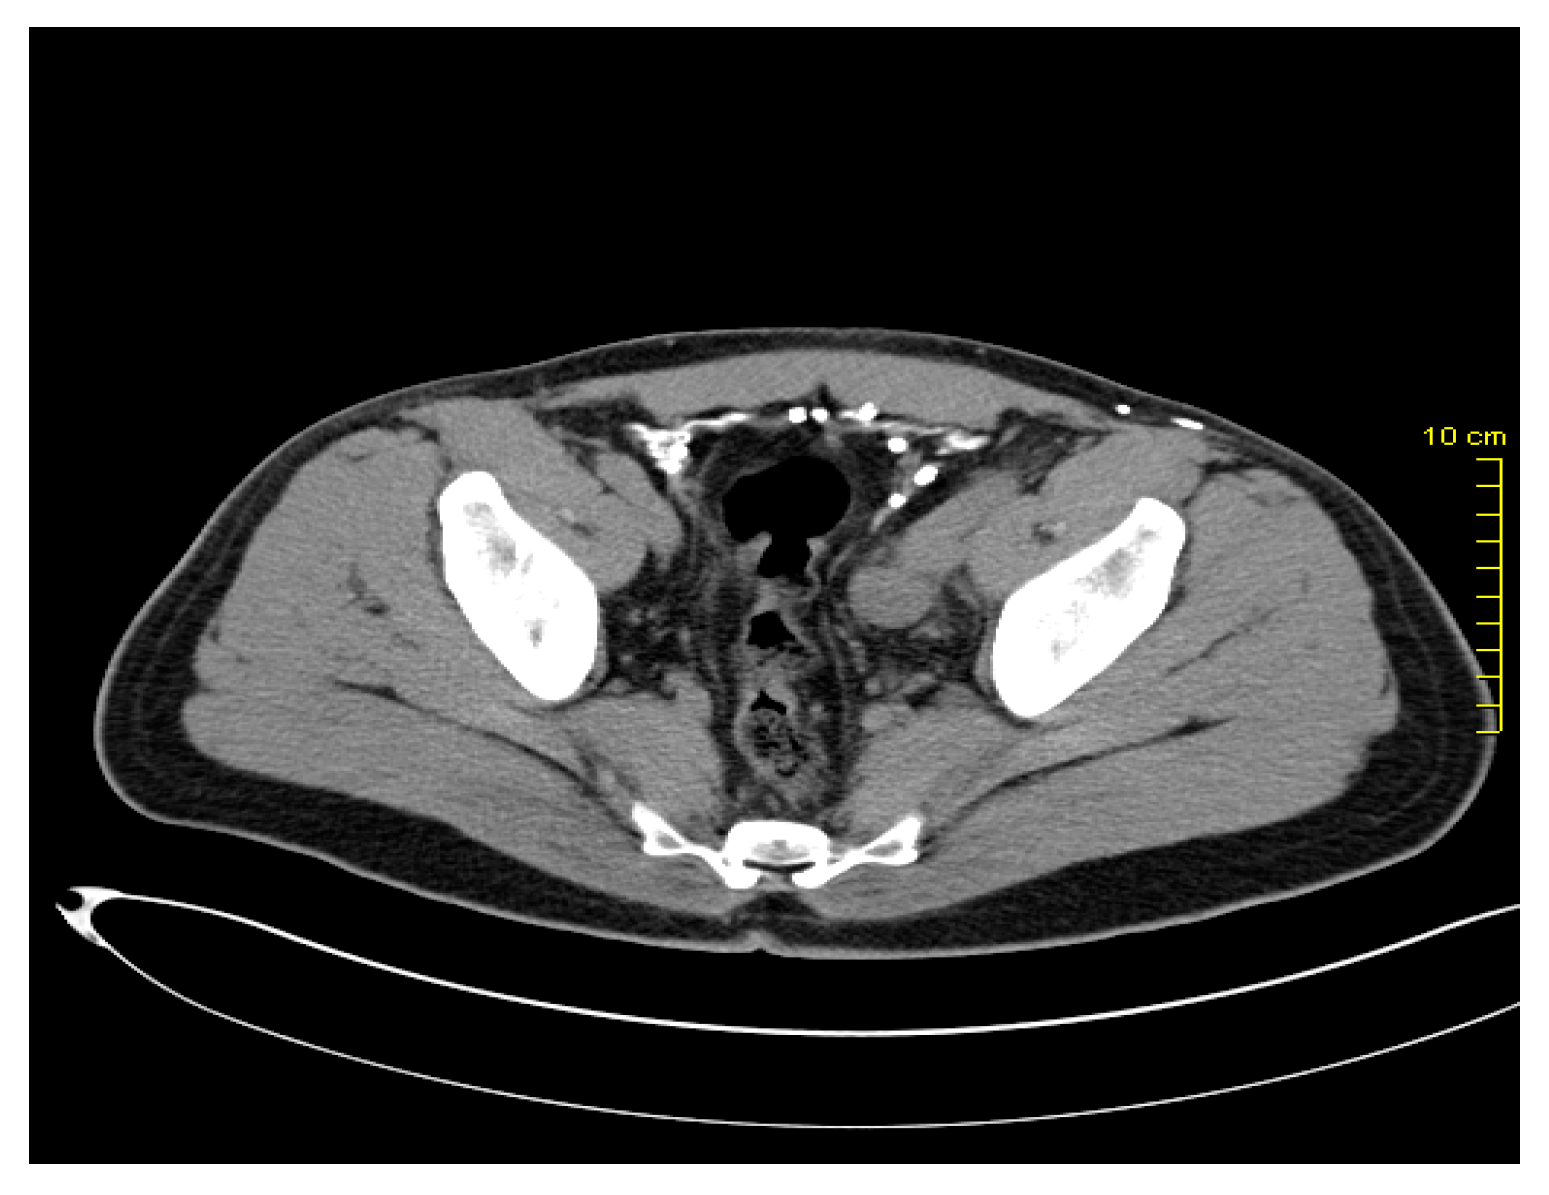

After two years, in March 2016, during the re-examination of the patient, pelvic lymphadenopathy was detected (Figure 1 and Figure 2), which, with the subsequent biopsy, was identified as disease progression with Vimentin(+), Melan C(+), S-100 (+), and AE1/AE3(-).

Due to disease progression, in May 2016, the patient started receiving an immunotherapy regimen as follows: Nivolumab 1 mg/kg and Ipilimumab 3 mg/kg every three weeks for four cycles, as well as maintenance immunotherapy with Nivolumab 3 mg/kg every two weeks. The patient responded to this new regimen with a significant regression of the lymph node metastasis, visible on imaging (Figure 3). During immunotherapy, the patient experienced adverse reactions. He presented grade I-II lethargy, grade I myalgia, and grade I-II diarrhea during Nivolumab + Ipilimumab combination therapy. Subsequently, with maintenance monotherapy, the patient developed grade I lethargy, grade I-II skin rash, grade I toxic ophthalmopathy, and hypothyroidism. These toxic effects were treated appropriately. Eye drops and topical corticosteroids were given for ophthalmopathy. Concurrently, the patient was treated with Levothyroxine, 50–75 μg/day. The patient remained in good condition with an excellent performance status (Karnofsky PS = 0) and continued to work during treatment.

Figure 2. Pelvic lymph node metastases.